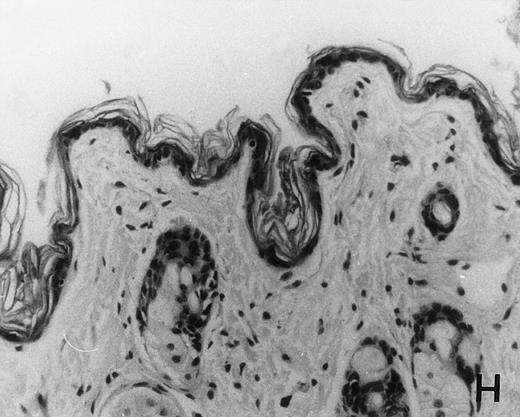

Previous in vitro studies showed that mdm100-specific, allo-restricted CTL killed H-2b tumor cells, including lymphoma cells, but not normal cells.24 However, only a limited selection of normal cells such as dendritic cells and Con-A–activated lymphocytes was available for in vitro tests. Thus, it remained unclear whether some normal tissues in vivo express sufficient levels of mdm-2 to trigger killing by the injected CTL. Several lines of evidence suggested that injected CTL did not attack normal host tissues. Firstly, none of the mice showed any acute side effects after CTL injection. Secondly, the recovery from BMT and the general health status were indistinguishable in mice that received CTL compared with control mice. Thirdly, histological analysis of liver, gut, and skin from 4 CTL treated and 4 untreated mice showed that these tissues, which are normally affected by GVHD, showed similar histology in mice with or without CTL administration (Fig 6). This indicated that CTL injection did not cause the tissue damage that is frequently seen in BMT individuals after infusion of allogeneic T lymphocytes.

Histology of BMT mice. (A through D) The histology of C57BL/6 mice transplanted with B10.A(4R) BM. One group of mice was injected with allo-restricted CTL while the control group did not receive CTL. (A) Liver from a CTL-treated mouse 3 weeks posttransplant, with no significant inflammation or necrosis. (B) Liver from a control mouse 3 weeks posttransplant, with mild periportal inflammation. Skin from a CTL-treated mouse (C) and a control mouse (D) 3 weeks posttransplant, with no significant inflammation or keratinocyte necrosis. Tissues were also examined at 4, 5, and 6 weeks posttransplant and showed no evidence of GVHD in either CTL-treated or control mice (not shown). (E-H) show the histology of (C57BL/6 × BALB/c) F1 mice, transplanted with BM from littermates. One group of mice was injected with allo-restricted CTL and a control group did not receive CTL. (E) Liver from a CTL-treated mouse 4 weeks posttransplant, with no significant inflammation or necrosis. (F) Liver from control mouse 4 weeks posttransplant, with no significant inflammation and necrosis. Skin from a CTL-treated mouse (G) and a control mouse (H) 4 weeks posttransplant, with no significant inflammation or keratinocyte necrosis. Tissues were also examined at 3 and 5 weeks posttransplant and showed no evidence of GVHD in either CTL-treated or control mice (not shown). (All H&E-stained sections, original magnification × 20.) Sections from colon and stomach also showed no significant inflammation (not shown).

We explored whether immune responses of BMT C57BL/6 hosts against BALB/c-derived CTL prevented the induction of GVHD by injected CTL. If this were the case, we predicted that CTL injection into (C57BL/6 × BALB/c) F1 hosts would result in GVHD. Thus, (C57BL/6 × BALB/c) F1 mice were transplanted with BM from littermates using the same conditioning protocol that was used for all experiments in this study. One group of transplanted mice was injected with 1.5 × 107 allo-restricted CTL and a control group did not receive any CTL. Histology of skin, liver, stomach, and gut performed after 3, 4, and 5 weeks showed that injected CTL did not cause GVHD in these F1 hosts (Fig 6E through H). Thus, lack of GVHD was not dependent on host immune responses against injected CTL.